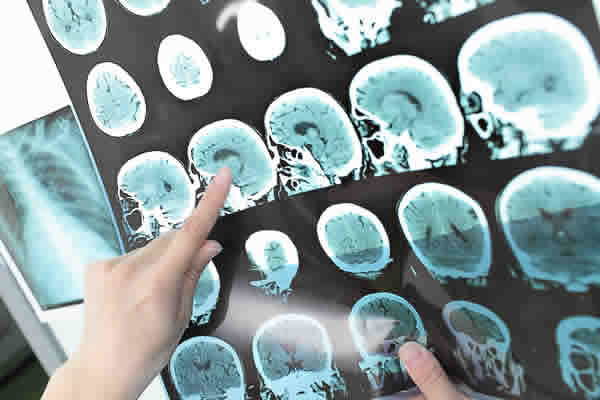

“Se tivesse uma conscientização maior, nós, pessoas com esclerose, não sofreríamos tanto, passando por todos esses problemas. Se eles tivessem descoberto, desde o início, essa minha doença, eu não teria perdido a minha visão, eu não teria múltiplas sequelas igual eu tenho, tanto no cérebro, quanto na coluna. Conheço outras pessoas que passaram pelo mesmo problema”, afirma.

De acordo com a Associação Brasileira de Esclerose Múltipla (Abem), a EM é uma doença neurológica crônica e autoimune — as células de defesa do organismo atacam o próprio sistema nervoso central, provocando lesões cerebrais e medulares. A doença não tem cura. No entanto, existem tratamentos que consistem em atenuar os sintomas e desacelerar a progressão.

A esclerose múltipla é uma doença inflamatória que atinge o cérebro e a medula espinhal. Os sintomas incluem fadiga, fraqueza muscular, visão turva, tremores, formigamento e confusões mentais. É autoimune, ou seja, ocorre quando o sistema imunológico ataca as células do próprio organismo. A doença não tem cura, mas com tratamento médico é possível evitar a incapacitação e ter boa qualidade de vida. A neurologista Claudia Piccolo explica como é feito o diagnóstico.